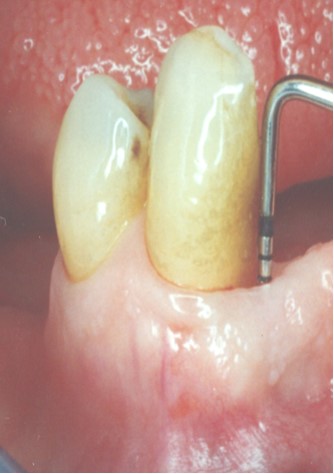

Parodontitis (Slika 1) podrazumijeva gubitak pričvrsnog aparata zuba koji bez terapije dovodi do gubitka zuba.